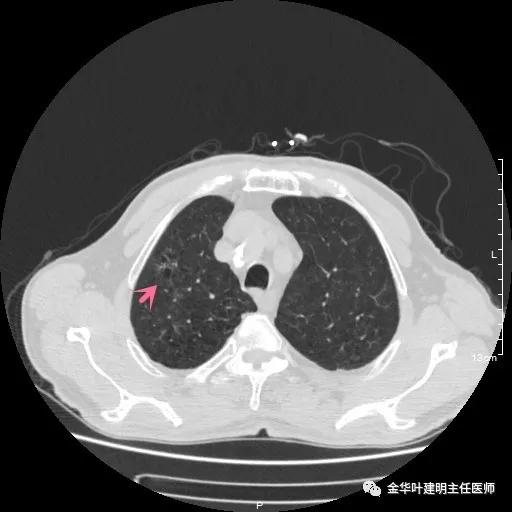

以上示右上病灶,我们称其病灶1。为囊腔型病灶,边缘为磨玻璃影,且轮廓清楚,局部有点状高密度,需考虑为囊腔型肺癌。单纯从单一病灶来看,这样的年纪可以随访或局部切除。